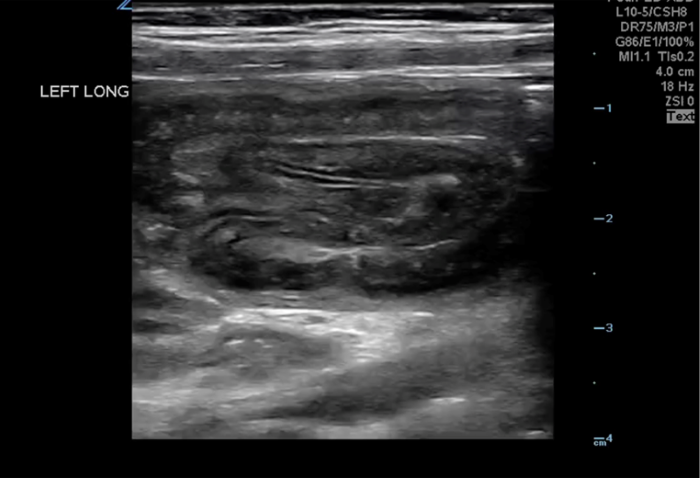

The linear probe is placed in the RLQ in the transverse position with indicator to the patient’s right. Identify the psoas muscle and iliac vessels lying medial. Once these structures are visualized, slide lateral and look superficially to identify the cecum. (Figures 1a,1b 1) Use graded compression-progressive increase and decrease of pressure to move any gas out of view. Keeping the lateral edge of the abdominal cavity in view (Figure 2), the ultrasound probe should slide cranial in traverse plane, visualizing the ascending colon until the hepatic flexure.  In this location, the colon turns just medial to the liver with the kidney deep in the view. (Figure 3) This is the most common location to identify ileocolic intussusception. If no tissue mass is identified, the probe should be turned to the sagittal plane with indicator toward the head (to keep the colon visualized in the transverse view) and moved across the transverse colon continuing to use graded compression to look for a tissue mass consistent with intussusception. Once at the splenic flexure (Figure 4), the probe should be transitioned back to the transverse orientation to interrogate the descending colon.

The abnormal structure of intussusception is a rounded tissue mass in the transverse axis with a hyperechoic center and hypoechoic outer muscle layer (Figure 5) and in long axis appears as a “pseudokidney.” (Figure 6) Outer dark edge to edge should be at least 2cm.1-3 Smaller structures with similar appearance are likely ileo-ileal intussusception, which is usually psychologic and does not typically require intervention.

10-2024 Article7-4.jpgFigure 4 LUQ Colon perimeter with kidney and edge of peritoneum in view.

10-2024 Article7-6.pngFigure 6. Long axis Intussusception, sometimes referred to as the “Pseudokidney” as it mimics the kidney’s shape in sagittal.